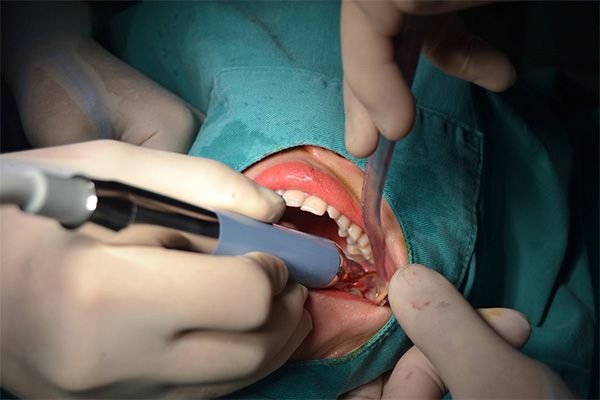

Nhổ răng khôn không còn là nỗi ám ảnh với công nghệ Piezotome tiên tiến tại Nha khoa Hanseoul. Piezotome là thiết bị sử dụng sóng siêu âm có tần số cao, giúp cắt xương và tách răng một cách chính xác, nhẹ nhàng, hạn chế tổn thương đến các mô mềm và dây thần kinh xung quanh.

Nhờ đó, phương pháp nhổ răng bằng Piezotome mang lại nhiều ưu điểm vượt trội:

Tại Hanseoul, việc ứng dụng công nghệ Piezotome kết hợp cùng quy trình vô trùng nghiêm ngặt và bác sĩ chuyên môn cao, đảm bảo mang đến cho khách hàng trải nghiệm nhổ răng an toàn, hiệu quả và thoải mái.

Bước 4: Nhổ răng bằng công nghệ Piezotome

Máy nhổ răng siêu âm tách răng nhẹ nhàng, hạn chế tổn thương mô mềm, ít chảy máu, ít sưng.